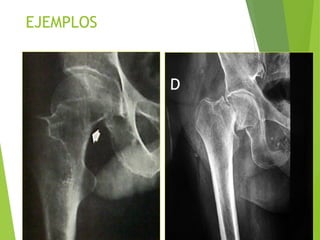

EJEMPLOS

Fx Subcapital cadera y NA

Necrosis avascular